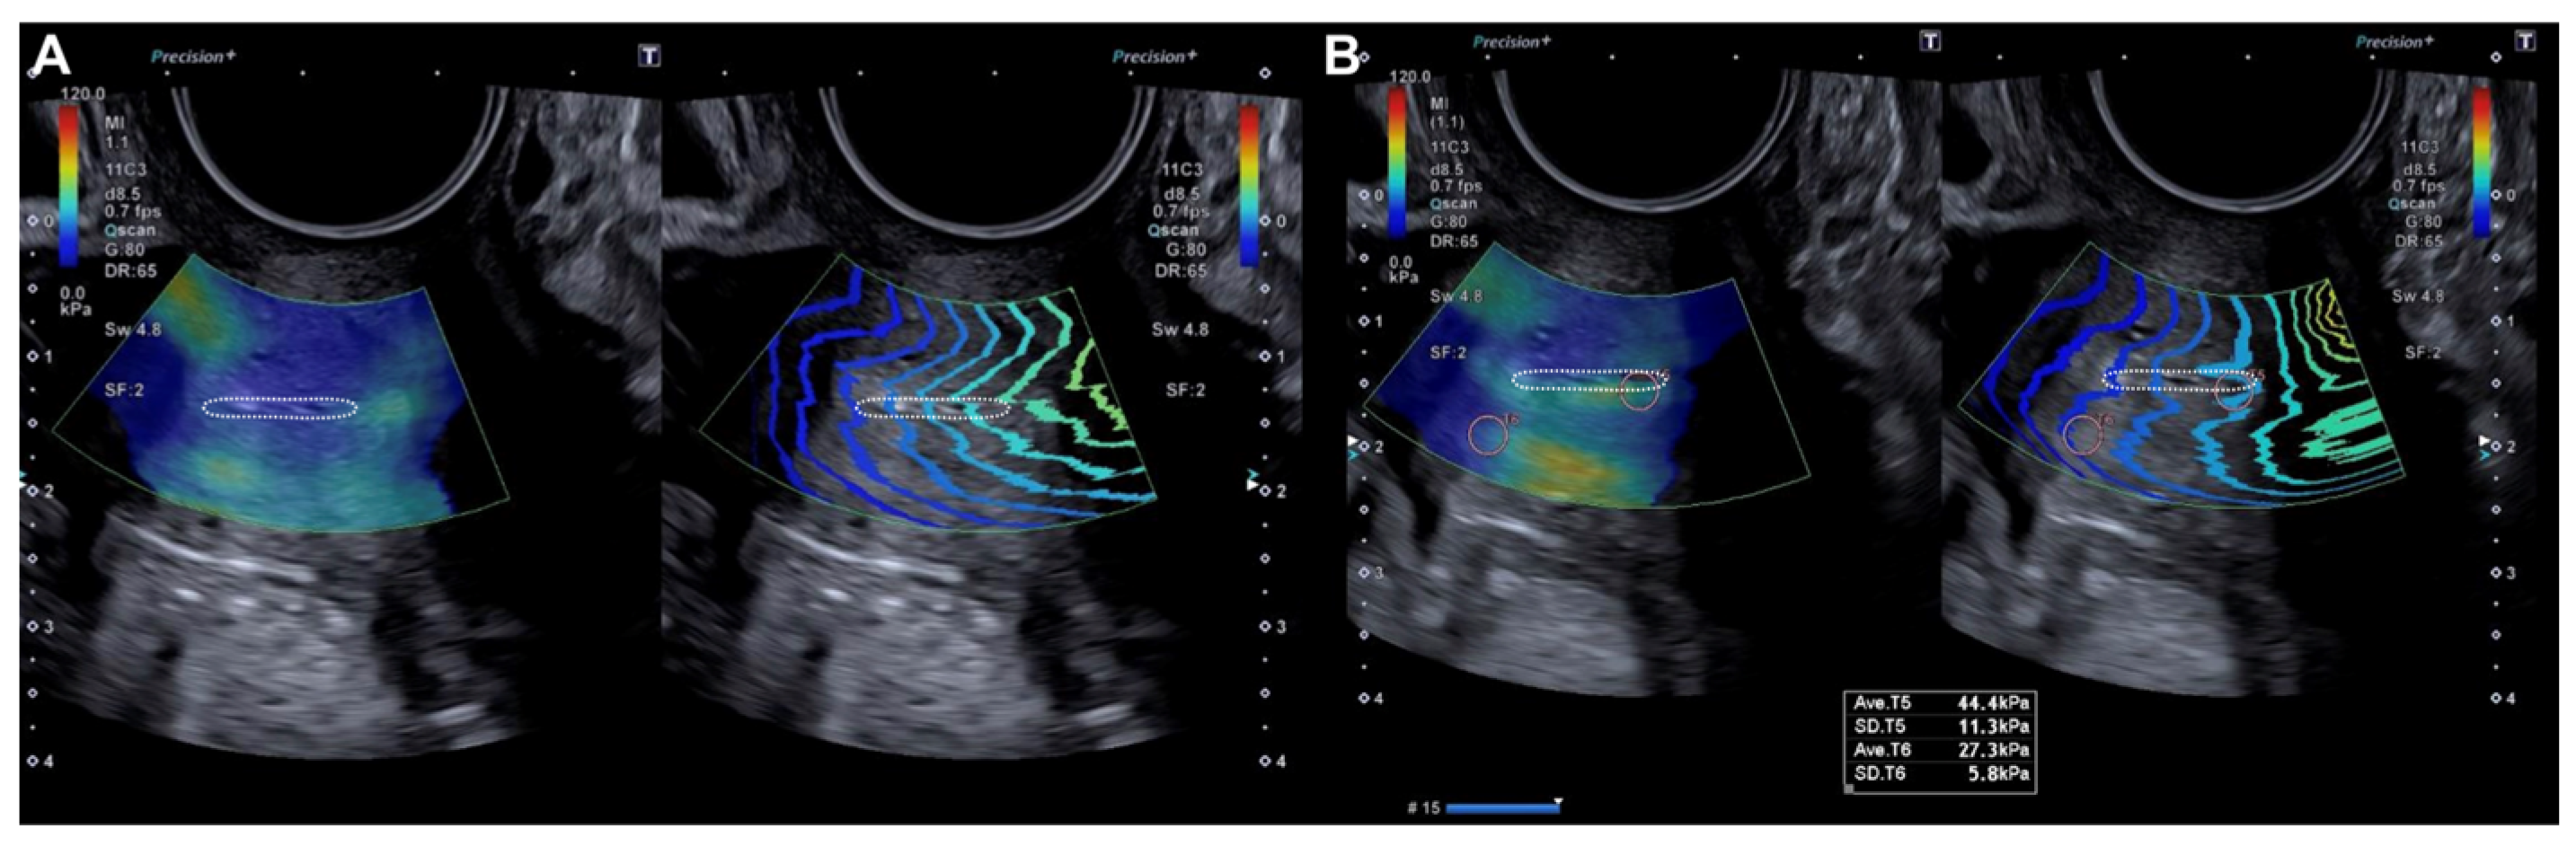

Figure 1.

Longitudinal assessment of the cervix (dotted line) by elastography (SonoElastoColposcopy). (A) A cervix with low stiffness (blue) and an adequate transmission wave control (in parallel). (B) Quantitative assessment of the stiffness measured in Kilopascals (Kpa).

The probe was subsequently rotated 90º and the external cervical os (ECO) was identified in the transverse section of the cervix using 2D ultrasound. In this transverse location of the ECO, elastography was reactivated and a new qualitative assessment was performed, identifying areas of increased stiffness (red color) (Figure 2). A quantitative assessment of the areas of increased (red) and decreased stiffness (blue) was then performed (Figure 2). Lastly, the locations of the lesions were described according to the model previously used in colposcopy.

Figure 2.

Transverse evaluation of the uterine cervix at the level of the OCE (dotted line) by elastography (SonoElastoColposcopy). (A) A cervix with low stiffness (blue) and an adequate transmission wave control (in parallel). (B) Quantitative assessment of the stiffness measured in Kilopascals (Kpa).